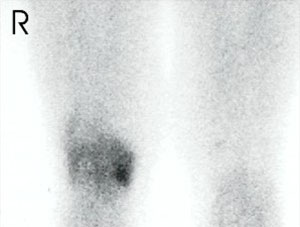

Dieses ist eine Szintigraphie der Kniegelenke.

Das Bild zeigt eine Entzündung [Arthritis] des rechten Kniegelenkes mit Maximum am inneren Anteil [medial], sehr wahrscheinlich als Folge eines Verschleißes [mediale Gonarthrose]. Das linke Kniegelenk ist unauffällig.